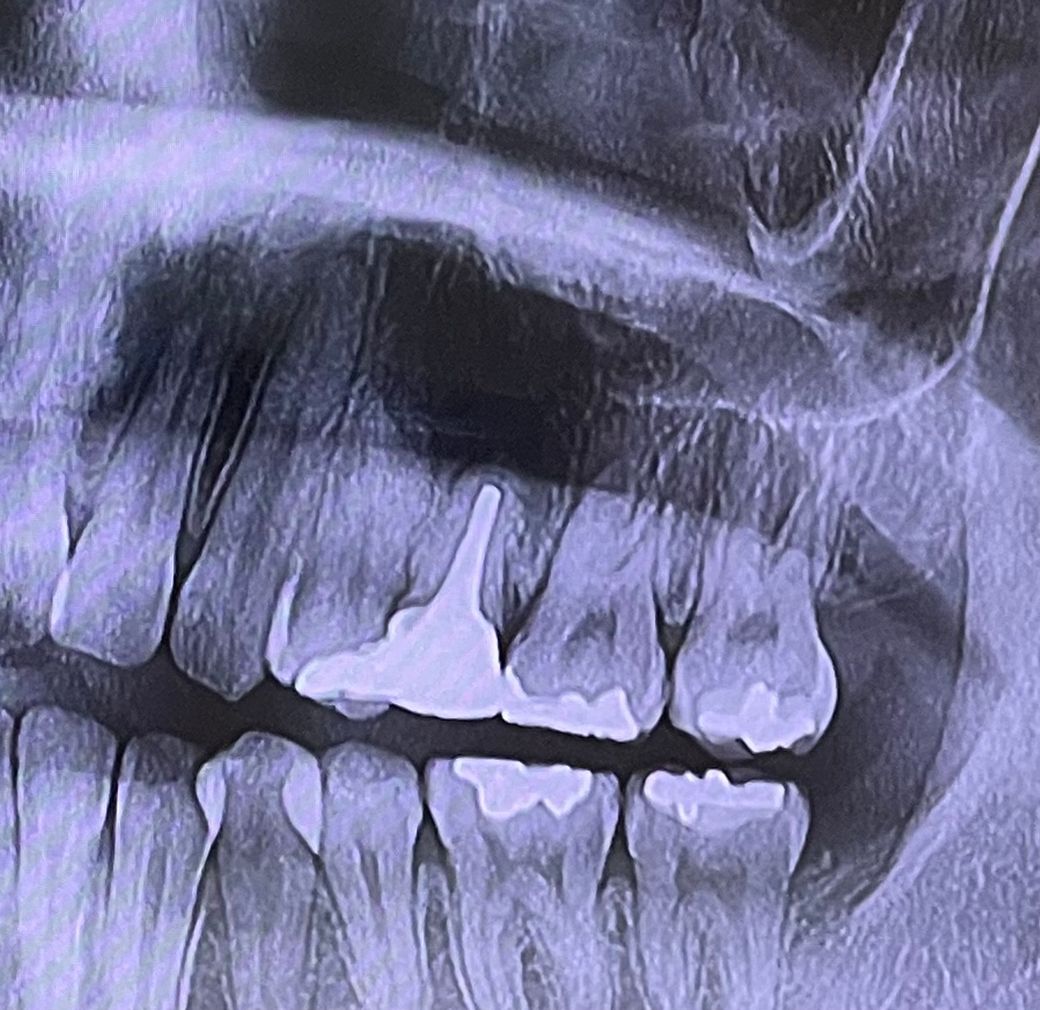

옛날에 치아에 포스트를 세우고 크라운을 씌운 치아가 크라운 씌운지 오래돼서 교체를 하였습니다 지르코니아로 포스트 기둥은 그대로 두고 크라운만 교체를 하였는데 크라운 교체할 때 망치 같은 걸로 뽑고 교체 르루 했는데 그 이후부터 잇몸이랑 주변 부위에 통증이 너무 심합니다 그래서 치과를 방문하니 치아 뿌리 쪽에 염증이 생겼다고 했는데 교체하기가 충격으로 인해 생긴 건가요? 그래서 어떻게 해야 하나 여쭤보니 여기서 손을 더 대면 임플란트를 할 수 있으니 그대로 두 자고 하시더라고요 근데 제가 치아 뿌리 염증에 대해서 찾아보니 치근 단 절제술도 있고 잇몸을 열어서 염증을 긁어내는 치료방법도 있던데 왜 안 해주시고 그냥 쓰라고 하시는 건지 궁급합니다 그리고 무조건 임플란트밖에 방법이 없다고 하셔서 정말 그런 건가요 그대로 두고 더 써보자고 하시는데 점점 염증도 커지고 나중에는 더 심해져서 위에 치근단 치료 같은 것도 못 받는 게 아닌지 궁급합니다 통증도 점점 심해지고 주변 치아까지 망가지는 게 아닌지 걱정됩니다 어떤 치료를 받아야 할까요 사진 첨부합니다

• 1번 째 사진